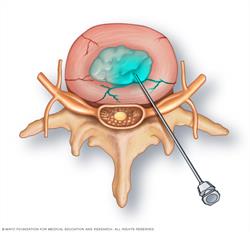

Discogram injection

Your healthcare team inserts the tip of a needle into the center of each disk to be examined. A contrast dye is then injected into the disk.